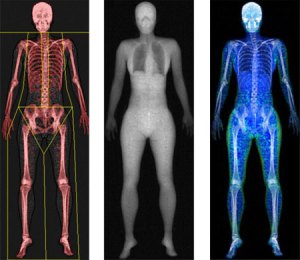

DEXA scans, what is the benefit of getting more than one scan?

All of our clients at Body Measure know that DEXA scans are the gold standard for body composition. The most …

Not happy with your DEXA scan results? It’s not personal

We’ll be upfront. Having a DEXA scan can sometimes be a bit confronting. Knowing EXACTLY how much fat is on …

Get a picture of your bone health

How healthy are your bones? Do you even think about your bones? After all, bones are hidden away, just doing …